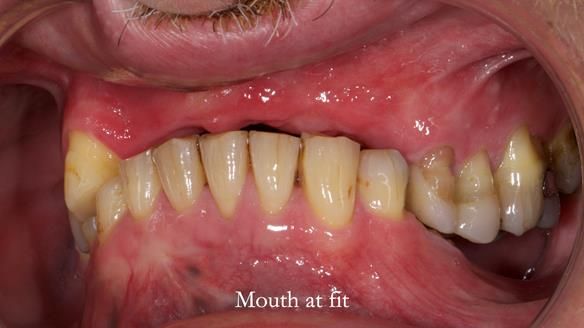

Keith’s case was one of the most challenging and rewarding cases I’ve treated this year. This 64 year old man presented with ill-fitting acrylic partial dentures that lacked stability, retention, and aesthetics. They constantly broke. He had lost the upper front teeth in a road traffic accident in his early 20s. The unopposed teeth had erupted, taking up space. After careful planning, we made a durable, metal-based upper partial denture/splint to address his dental concerns. He loved the outcome.

1. Denture design: A custom cobalt-chromium framework was Scandinavian-designed to maximise stability, protect the remaining teeth, and allow for future additions if needed.

2. Onlay preparations: Composite onlays were fitted for his upper left premolars to repair these teeth and support the new denture.

3. Definitive alginate impression in custom tray: Used to ensure a well-fitting RPD.

4. Keith’s outcome: The final denture not only improved Keith’s bite, chewing function, and facial aesthetics but also protected his remaining teeth from further damage.

What makes this case really interesting?

Keith’s denture incorporated a Duracetal shell clasp on upper right first premolar (Myerson), which are designed to be virtually visible, providing a more aesthetic solution while enhancing patient comfort. The Scandinavian-inspired approach, based in modern removable prosthodontic techniques, ensured the denture was not only durable but also visually pleasing. Additionally, the design was carefully planned to allow for future modifications, ensuring that if Keith loses additional teeth, the denture can be adapted rather than replaced entirely.

I also used the Dahl concept to re-establish the occlusion upon fitting the RPD, which helped to intrude the lower left canine without needing to grind it too much.